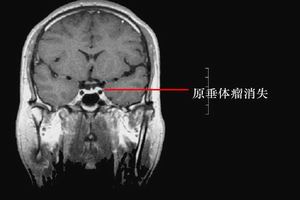

實驗室檢查:垂體CT、MRI檢查有快速而準確的診斷價值。可顯示垂體腫瘤以及瘤體內的出血區和壞死區,並可顯示腫瘤是否向鞍上和鞍旁生長。蝶鞍X線片可顯示蝶鞍擴大、破壞,有助診斷。

如瘤體出血或壞死組織漏進蛛網膜下腔,腦脊液呈血性,白細胞增多。外周血中白細胞總數及中性粒細胞增高。如存在腺垂體功能減退,則血中甲狀腺激素、促甲狀腺激素、皮質醇、促腎上腺皮質激素、促性腺激素、睪酮、雌二醇均降低。如垂體瘤為泌乳素瘤,血中泌乳素水平升高。如為分泌生長激素的腺瘤,血中生長激素(GH)水平升高。如為分泌ACTH的腺瘤,血中ACTH及皮質醇水平升高。其他輔助檢查:腺瘤性垂體卒中在頭顱平片上的表現為:蝶鞍擴大、鞍底變薄、破壞、鞍底骨折。蝶鞍擴大,鞍底變薄也見於非卒中的垂體腺瘤,故無特異性,只有與近期頭顱平片對照才有價值。鞍底骨折對垂體卒中的診斷具有特異性,但其發生率太低。在垂體腺瘤發生卒中的急性期,CT顯示出清晰的高密度圓形病灶,數天后病灶的密度逐漸降低。CT還可以顯示出血的量、出血是否破入蛛網膜下腔以及垂體周圍結構受累情況。MRI不能顯示急性出血,故在診斷時不作為首選。隨著紅細胞的破壞,脫氧血紅蛋白轉變為正鐵血紅蛋白。正鐵血紅蛋白可使T1和T2加權圖像的信號增強。故血腫的信號密度隨著時間的推移而逐漸增加,一般來說,7天以內的血腫在T1和T2加權圖像上均為低或等信號病灶(同周圍腦組織相比);7~14天血腫,其邊界信號增加,但血腫中心仍為低信號區;14天以後,整個血腫在T1和T2加權像上均為高信號灶。產後大出血所致垂體卒中的特點為垂體缺血、壞死,無出血,在影像學上表現為垂體的縮小。其他疾病引起的垂體卒中有相應的表現。